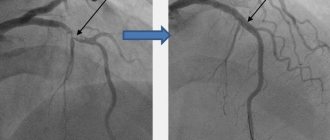

• дуплексное ультразвуковое сканирование;

• компьютерная или магнитно-резонансная томография головного мозга;

• ангиография.

Они позволяют точно определить локализацию гематомы и ее размер, наличие бляшек. А также оценить текущее состояние кровотока, что в итоге помогает нейрохирургу определиться с объемом операции. Стоит понимать, что большая гематома сама не рассосется, и если ее не удалить оперативно путем трепанации черепа, исход будет скорее всего летальным.